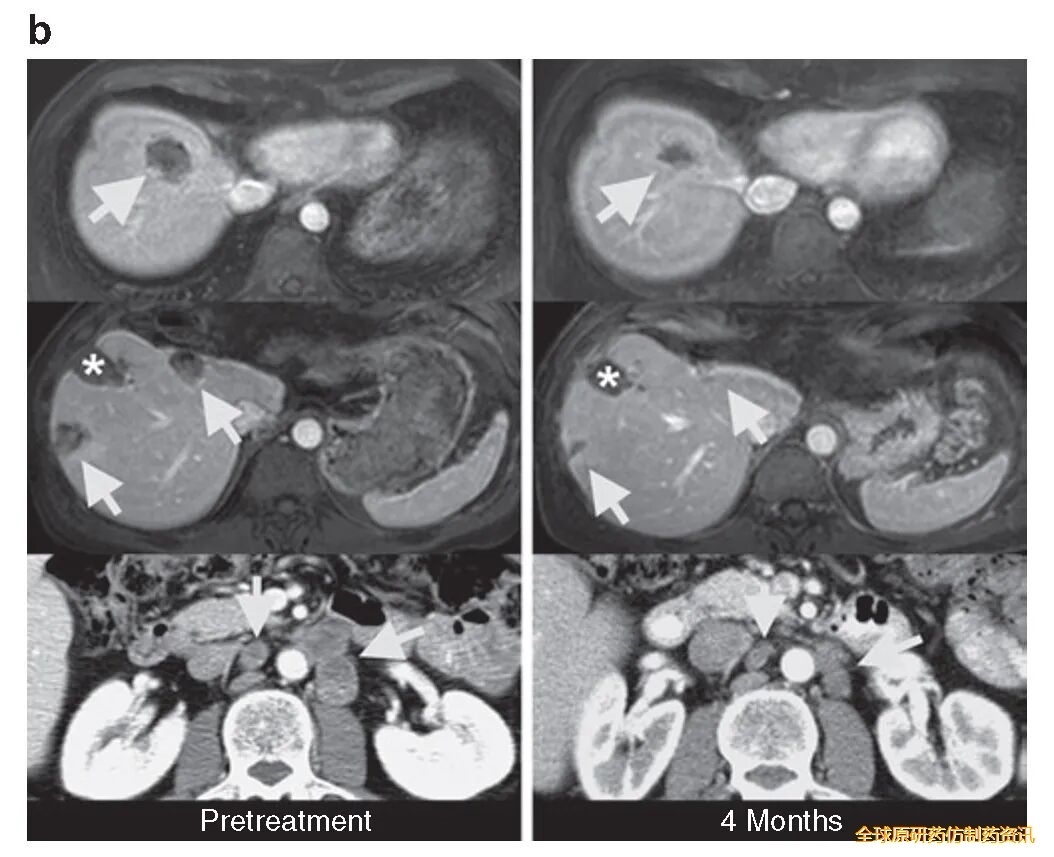

患者3在治疗3个月时,肝、肺及腹主动脉旁淋巴结转移瘤按实体瘤疗效评价标准(RECIST)缩小34%,4个月时缩小幅度达49%(详见下图),达到RECIST确认的部分缓解(PR)。

▼患者3在治疗前、治疗后4个月的计算机断层扫描(CT)图像

▲图源“Mol Ther”,版权归原作者所有,如无意中侵犯了知识产权,请联系我们删除

注:

①箭头表示:结直肠癌转移灶的位置;

②星号表示:先前接受过射频消融(RFA)治疗的肝转移灶部位的肝脏缺损。